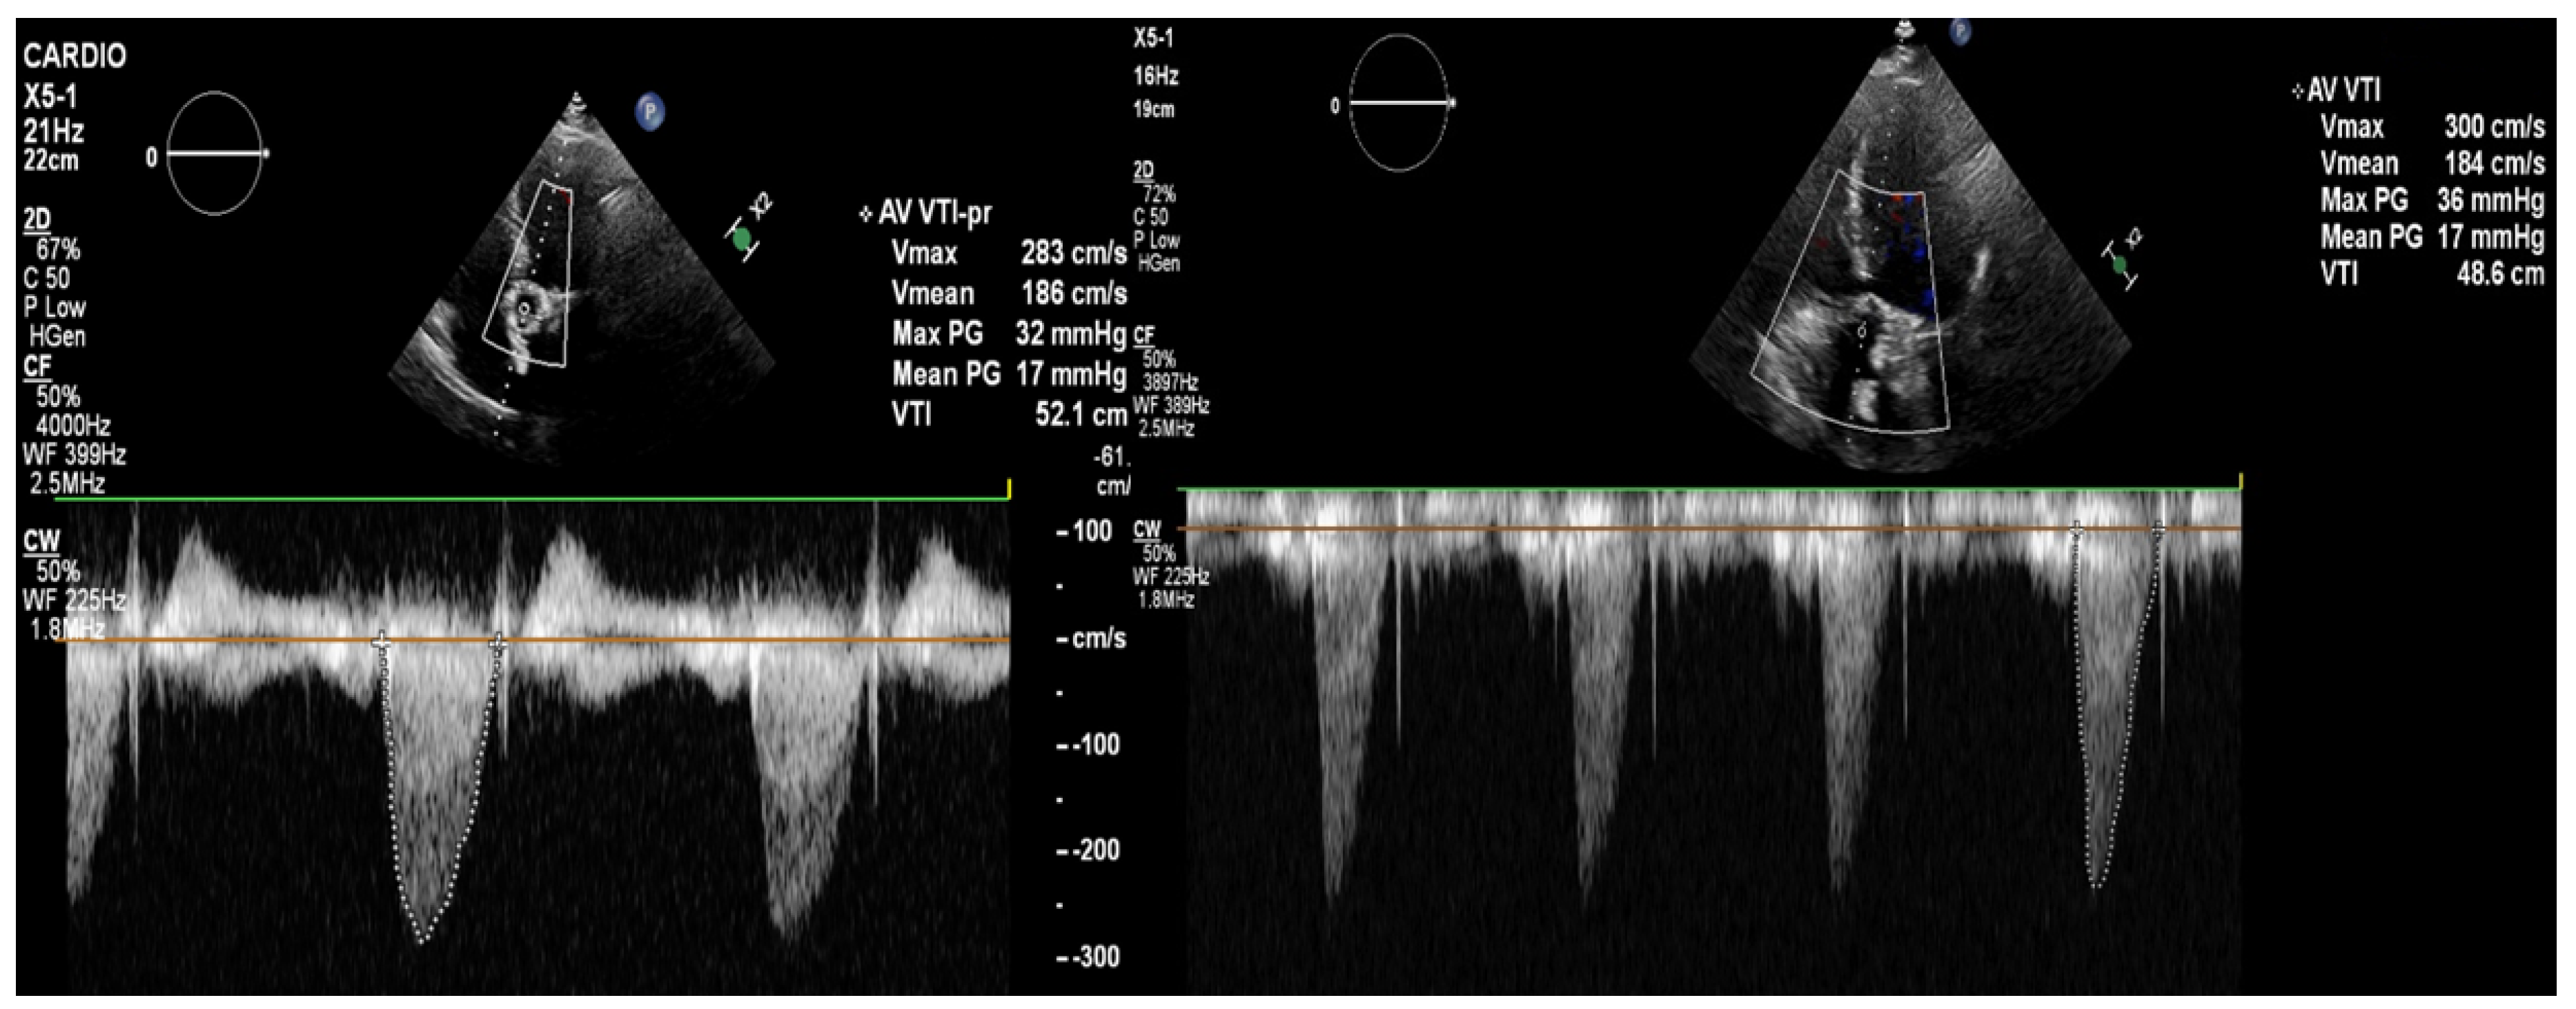

Figure 4. The transthoracic echocardiography showed a reduction in the gradients through the aortic valve prosthesis with parameters similar to that after the TAVI (on left: post-TAVI; on right: post-LMWH treatment). According to the 2021 ESC/EACTS Guidelines, in patients after TAVI, lifelong SAPT is recommended in the lack of indications for oral anticoagulants (OACs) [1]. However, despite similar recommendations for aspirin, the 2020 ACC/AHA Guidelines suggest that in patients with a low bleeding risk, it is worth acknowledging the antithrombotic prophylaxis with DAPT or VKA [2]. The direct-acting oral anticoagulants (DOACs) were not found to be superior to the administering antiplatelet or VKA, and in patients without indications for OAC, were linked to a higher incidence of all-cause mortality [3,4,5]. The 2021 ESC/EACTS and 2020 ACC/AHA Guidelines for managing valvular heart disease indicate that anticoagulation using VKAs or UFH is a first-line therapy for bioprosthetic valve thrombosis. Such an approach is highly effective in the normalization of valve function in 85% of the patients [6].